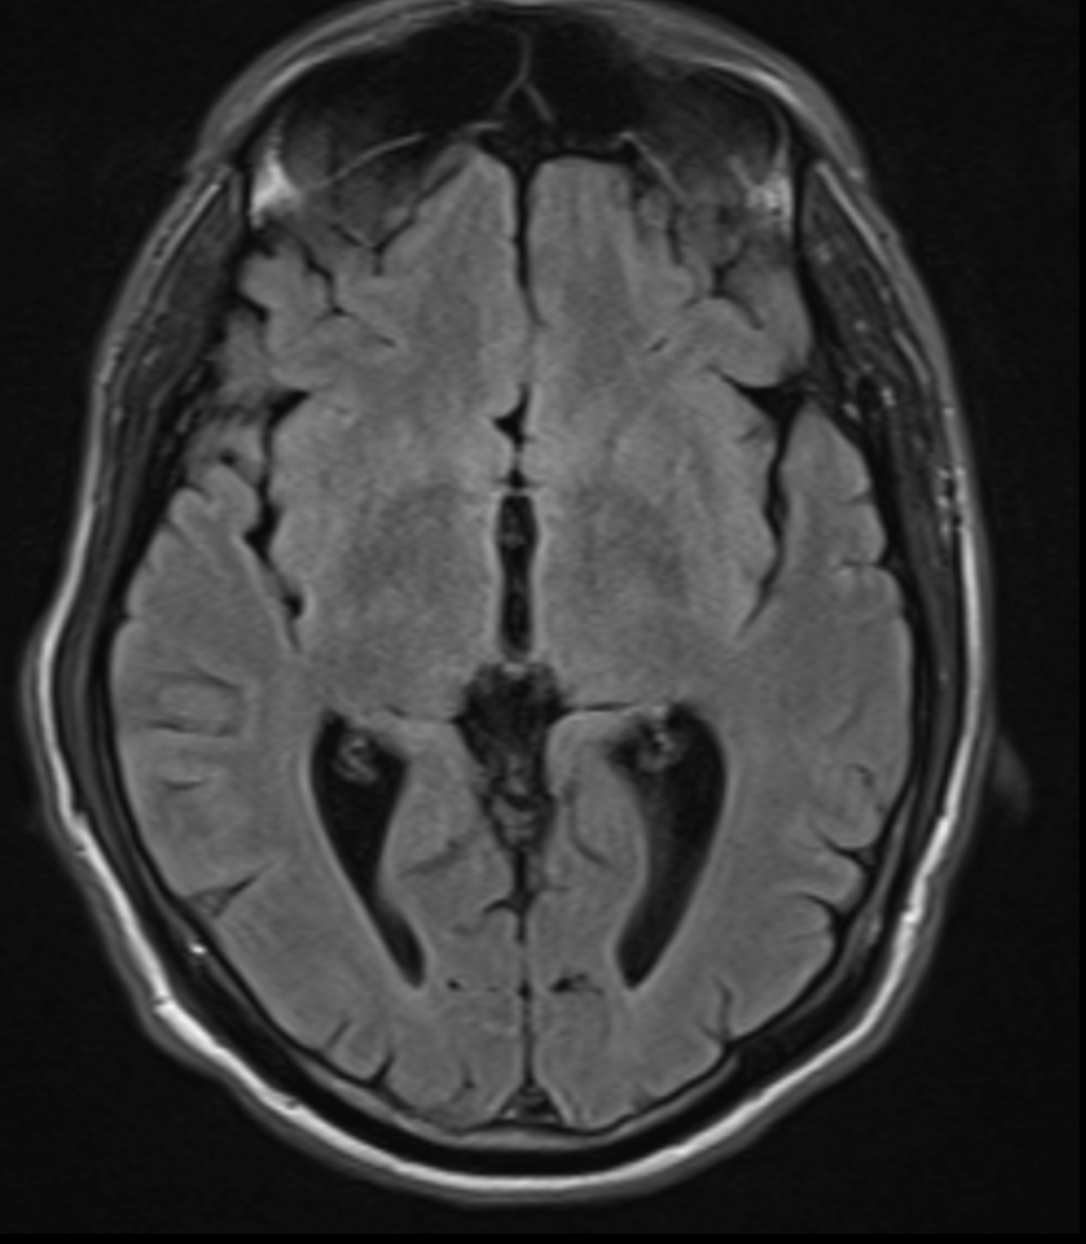

Quelle est la séquence de cet IRM ?

T2 Flair